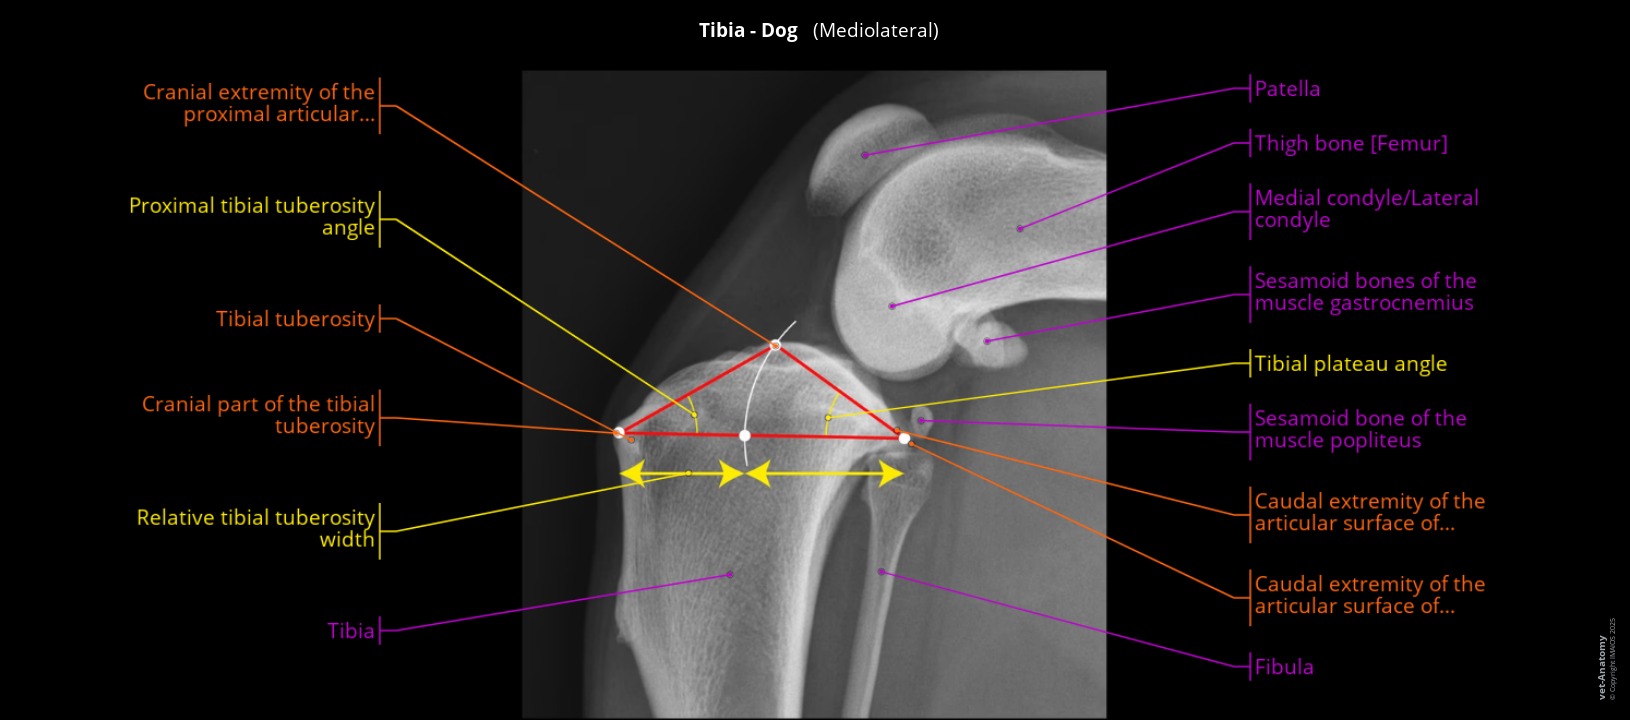

Anatomy of the dog's tibia and stifle in radiograph

Mediolateral radiographic view of the stifle showing the patella, the tibial plateau angle, and the tibia.